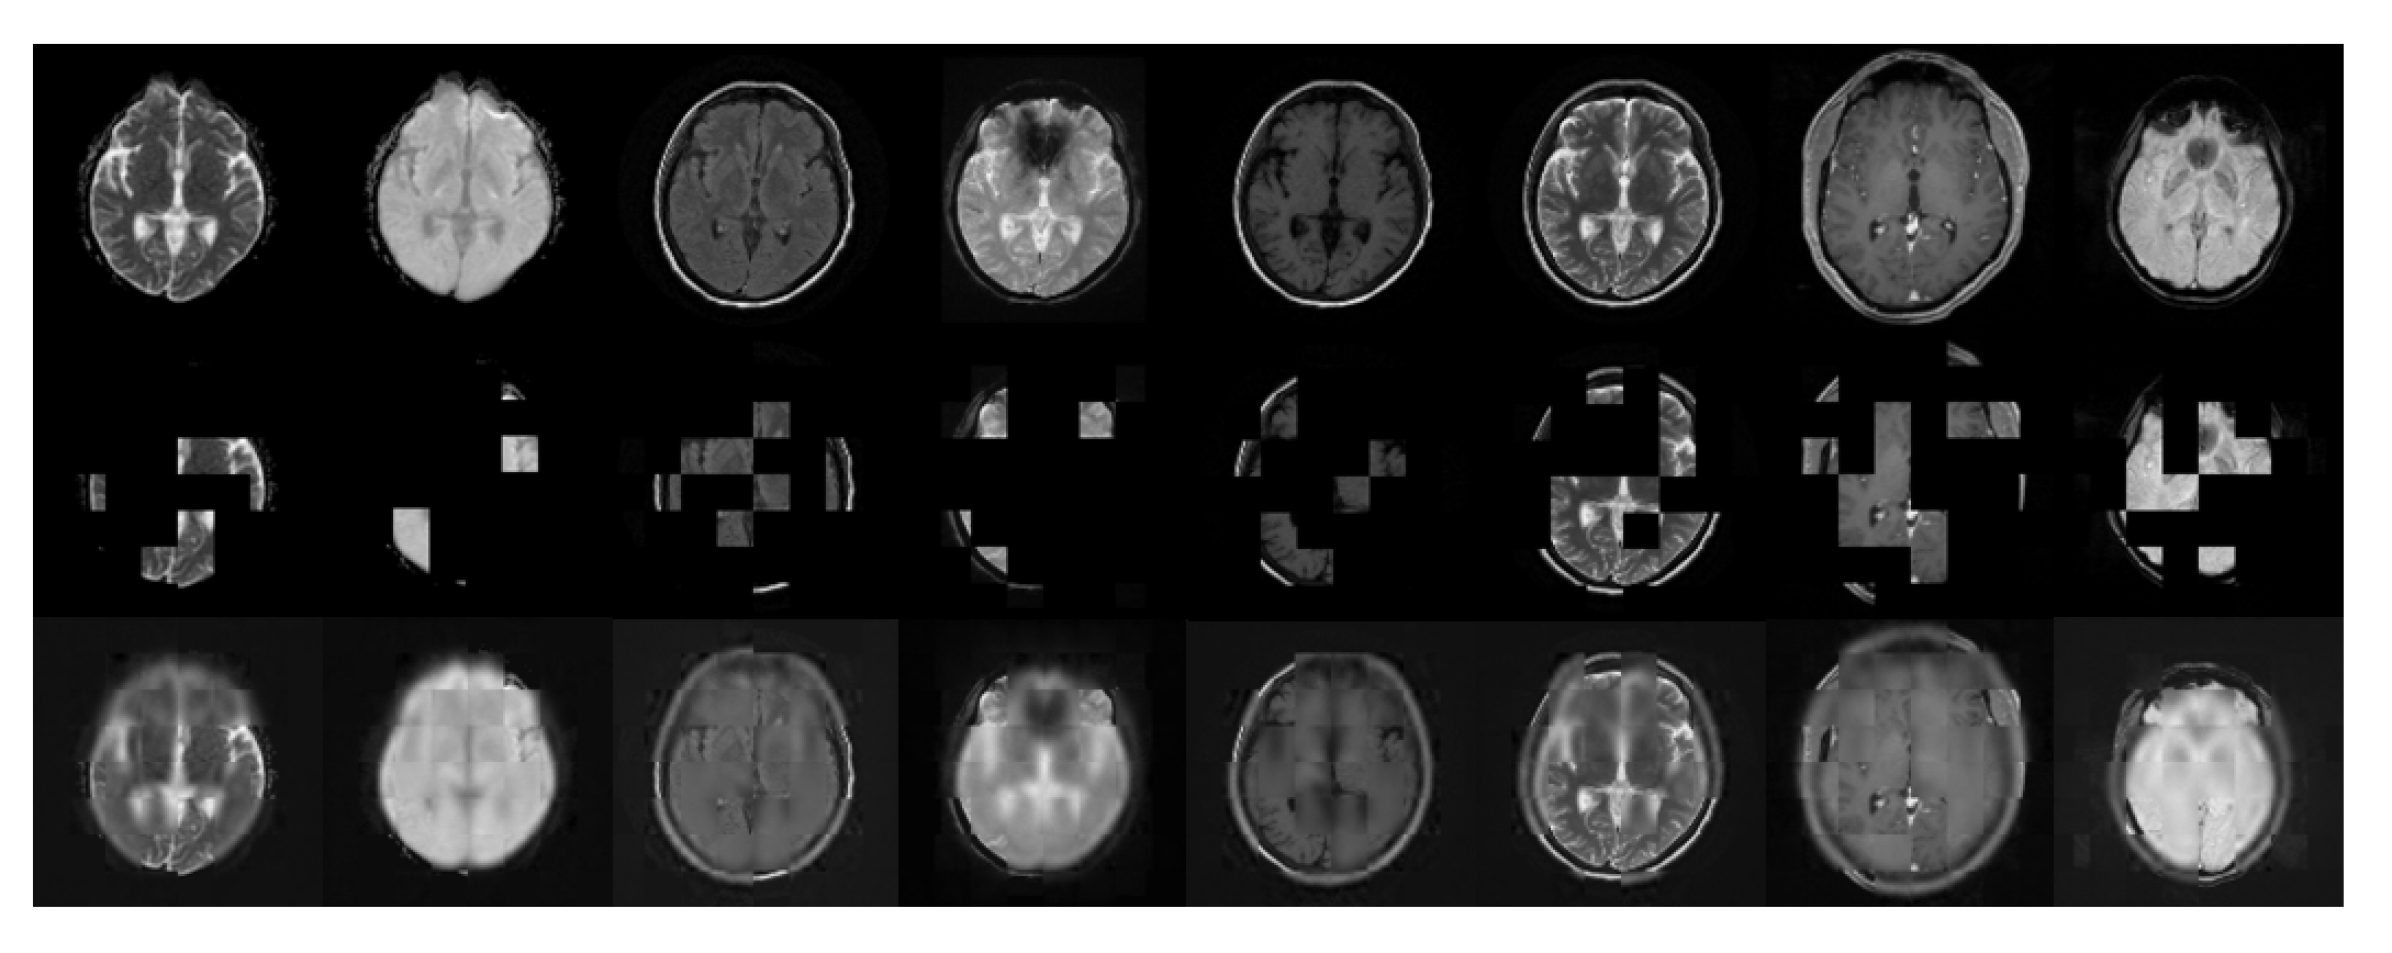

We further extended the AdaViT architecture for self-supervised pretrain using masked autoencoder. Our proposed AdaViT can accommodate variable set of input modalities for each case, enabling us to leverage all available cases with any sets of modalities for self-supervised pretrain. To investigate this, we first conducted self-supervised pretrain with our AdaViT on the SSL-pretrain dataset containing 45,374 cases, with up to 8 different modalities/contrasts for each case. We then finetuned the model for brain infarct and brain tumor segmentation tasks. The MAE style self-supervised pretrain reconstructions of ADC, TraceW, FLAIR, GRE, T1, T2, T1CE, and SWI with AdaViT are shown in Figure 3. The three rows consist of a single slice of the original input image of the above contrasts, their corresponding masked images, and the reconstructed images, respectively. The outcome shows that AdaViT masked autoencoders can recover randomly masked patches from the context. The recovered visible patches appear blurry due to L2 loss, which is a known phenomenon of MAE pretrain on 3D medical images [47]. In spite of the blurriness, the MAE reconstruction, as a self-supervised pretrain method, can learn to extract useful features benefiting the downstream tasks.